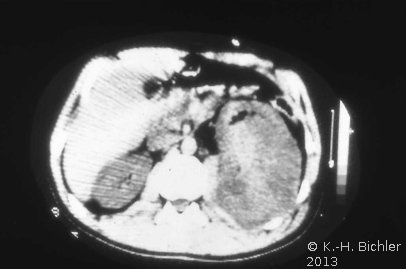

Von Wichtigkeit sind die bildgebenden Verfahren: Sonographie, CT bzw. AUR.

Beispielhaft die Darstellung eines ausgedehnten Nierenabszesses in Sonographie, CT und AUR (Abbildung 6).

Die Nierenfreilegung und Abszessdrainage bzw. der postoperative Krankheitsverlauf im obigen Fall (s. Abbildung 6) sind in den Abbildungen dargestellt (Abbildung 9,10).